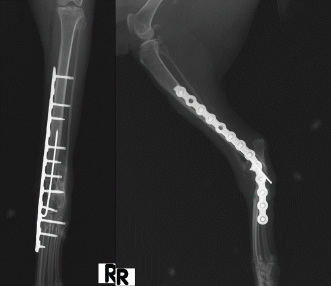

Case Details

Fig. 3. Craniocaudal and mediolateral postoperative radiographs after pantarsal arthrodesis showing good alignment of the tibia, tarsus, and metatarsus.